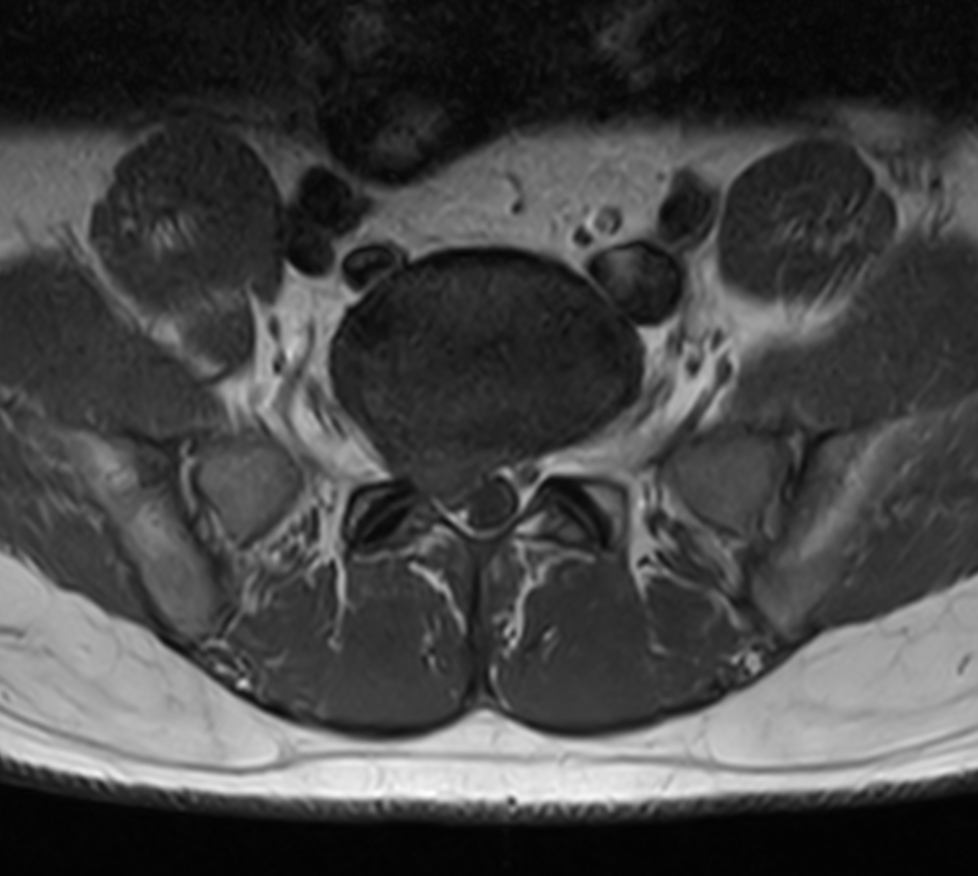

Lower back ache radiating to right lower limb. Diagnosis: Degenerative lower lumbar spondylosis, L5-S1 Stenosis

Axial T1w TSE